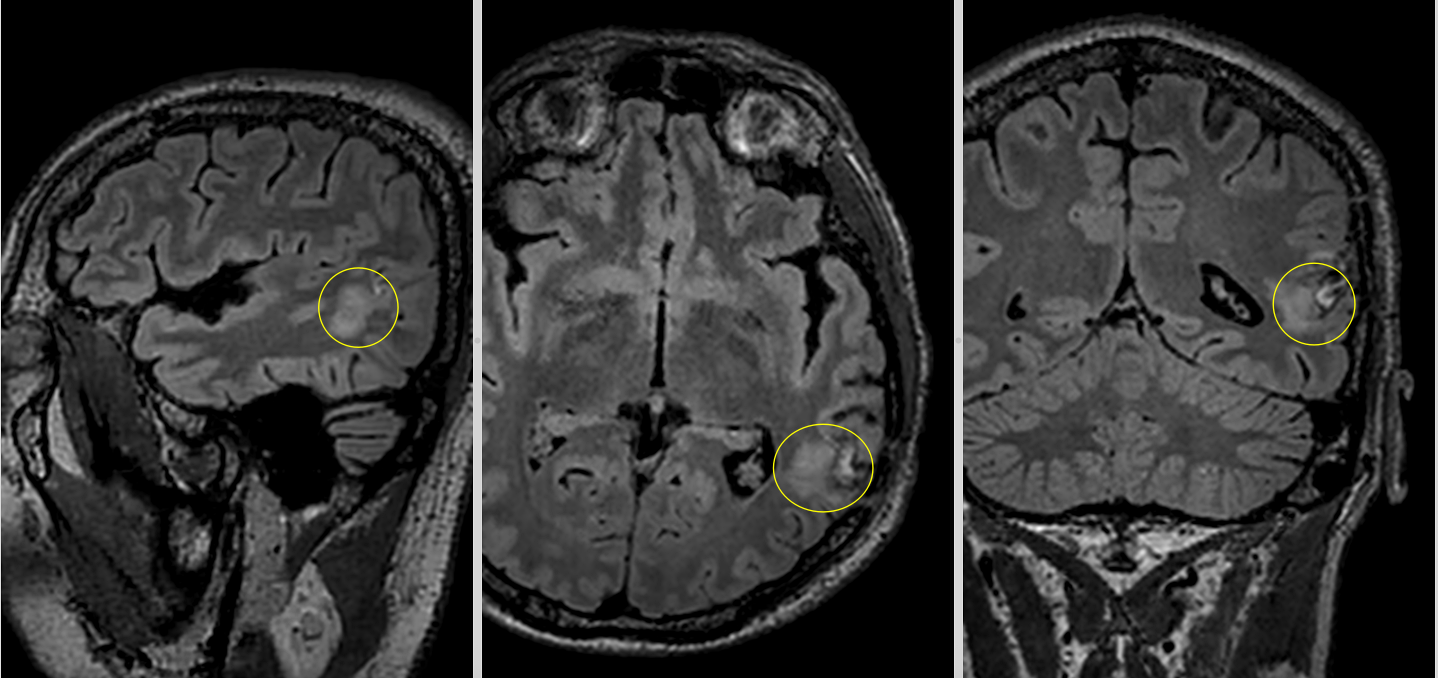

RMN-ul cerebral a evidențiat o tumoră temporală stângă cu semnal hiperintens în secvențele T2 și FLAIR, hiposemnal T1 și fără priză de contrast — un profil imagistic sugestiv pentru un gliom de grad mic.

Dincolo de imagini, adevărata provocare era localizarea. Tumora se afla în lobul temporal stâng, în vecinătatea unor structuri esențiale pentru limbaj. Analiza preoperatorie a arătat că leziunea infiltra și limita fasciculele lungi de asociație din substanța albă profundă a emisferului stâng. La polul superior al regiunii tumorale se afla aria Wernicke, cu rol crucial în înțelegerea limbajului. În profunzime și în vecinătate erau implicate rețele funcționale majore, în special fasciculul arcuat stâng, cu rol central în limbaj, și fasciculul fronto-occipital inferior (IFOF), important pentru integrarea semantică și cognitivă, pentru înțelegerea complexă a limbajului, dar și pentru integrarea informației vizuale.